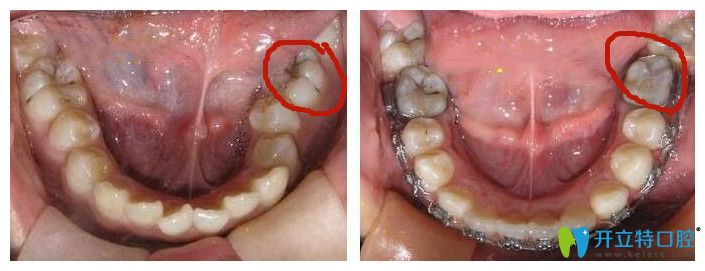

牙齒鎖合圖片

鎖合牙圖片

鎖合牙矯正對比圖